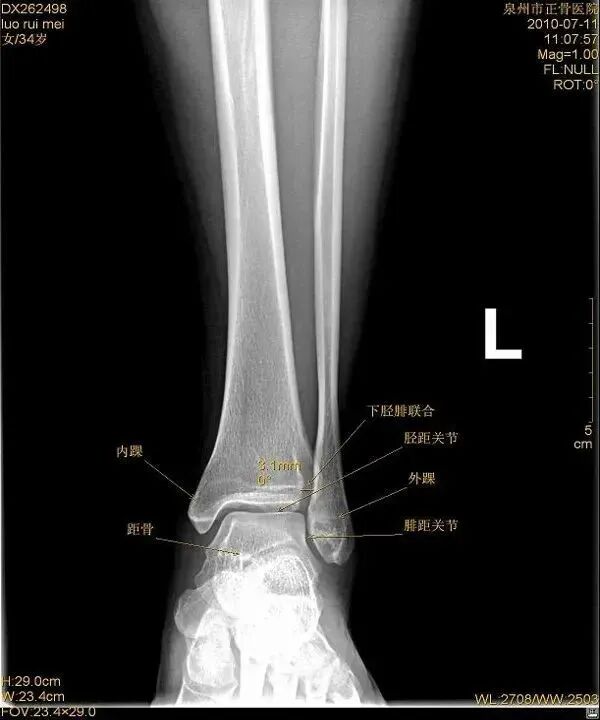

距骨在踝穴内有无倾斜,会通过影响关节面接触面积而影响关节所受应力的大小。有轻度倾斜,关节面所受到的应力会因为承重面积变小而明显增加。

外旋位扭伤受伤时距骨受到外旋外力,或小腿内旋距骨受到相对外旋外力。随着外旋暴力增大下胫腓联合主要韧带断裂,下胫腓联合分离。严重的多合并外踝骨折或内侧韧带断裂。